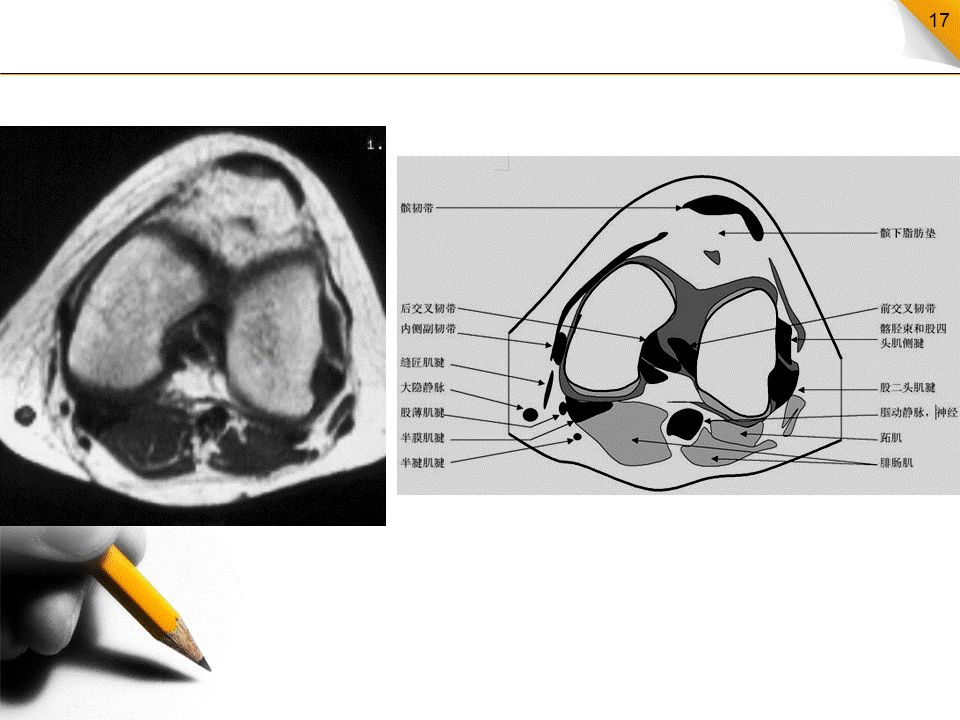

膝关节MR解剖(横断面)

是三维影像首选的方位,也是为了便于MRI与CT比较可准确地展现髌骨内外侧关节面